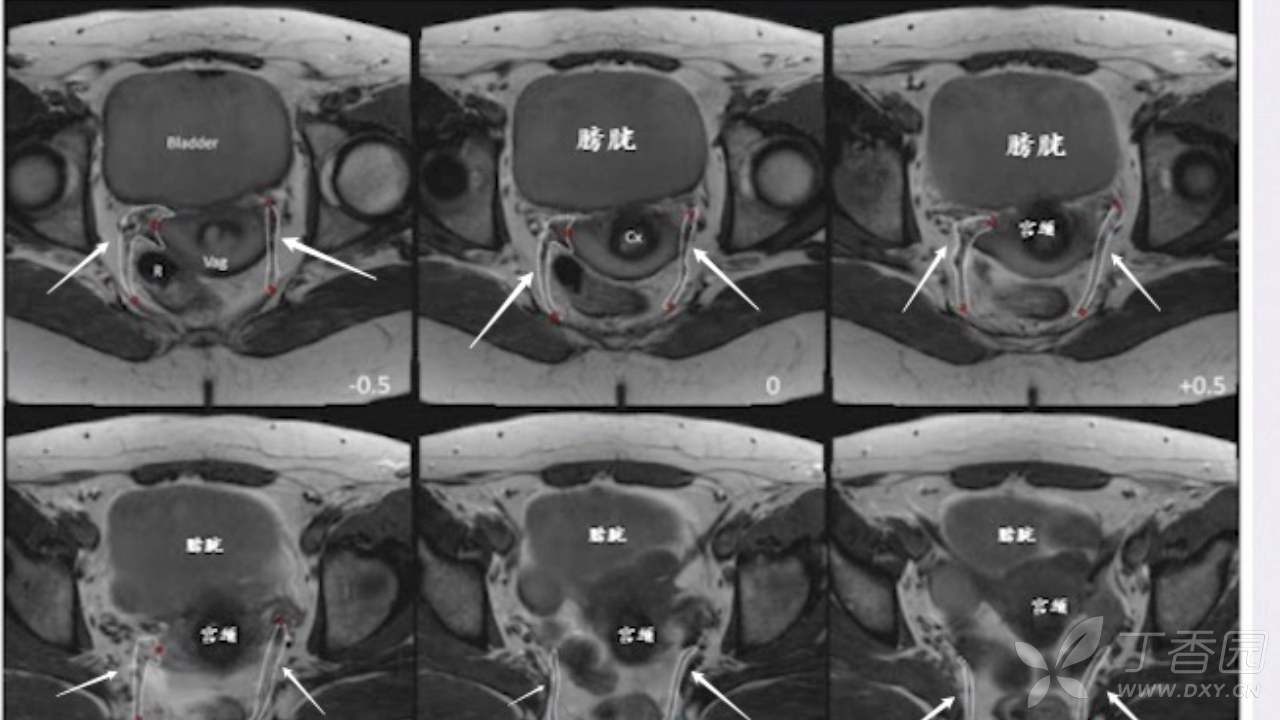

1 分钟学会盆腔韧带 MRI ,高清视频讲解

抽出 1 min,看懂子宫圆韧带 MRI 解剖,节假日弯道超车,你和主任的差距就又小了一点。